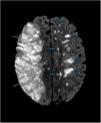

Primary central nervous system vasculitis. A rare disease with high mortality

Vasculitis primaria del sistema nervioso central. Una enfermedad rara con alta mortalidad